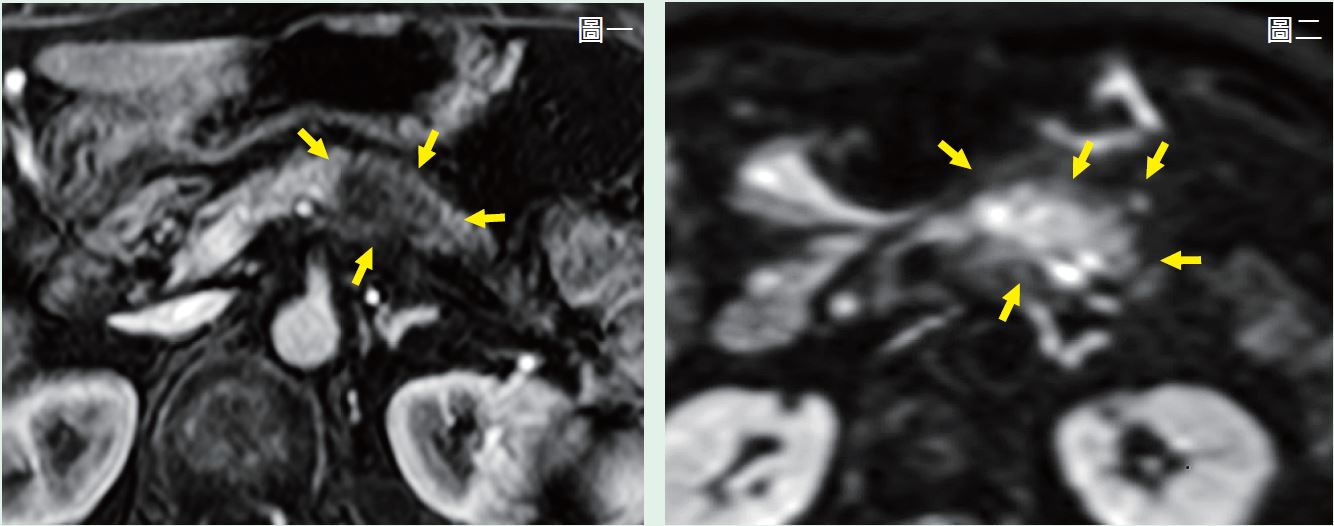

65歲女性,患有糖尿病,近來有上腹痛症狀,躺下後症狀加劇,甚至影響到睡眠,健康檢查發現CA19-9升高(214.65,正常值<37),醫師建議以MRI做進一步評估。施打顯影劑之動態掃描MRI,是針對胰臟絕佳的非侵入性影像檢查,可精確偵測胰臟腫瘤。

圖一顯示在胰臟的體部有一顯影不佳的不規則腫塊,大小約4.8×2.0公分,在圖二擴散影像中則顯示相對應位置有異常的高訊號,後證實為胰臟癌。